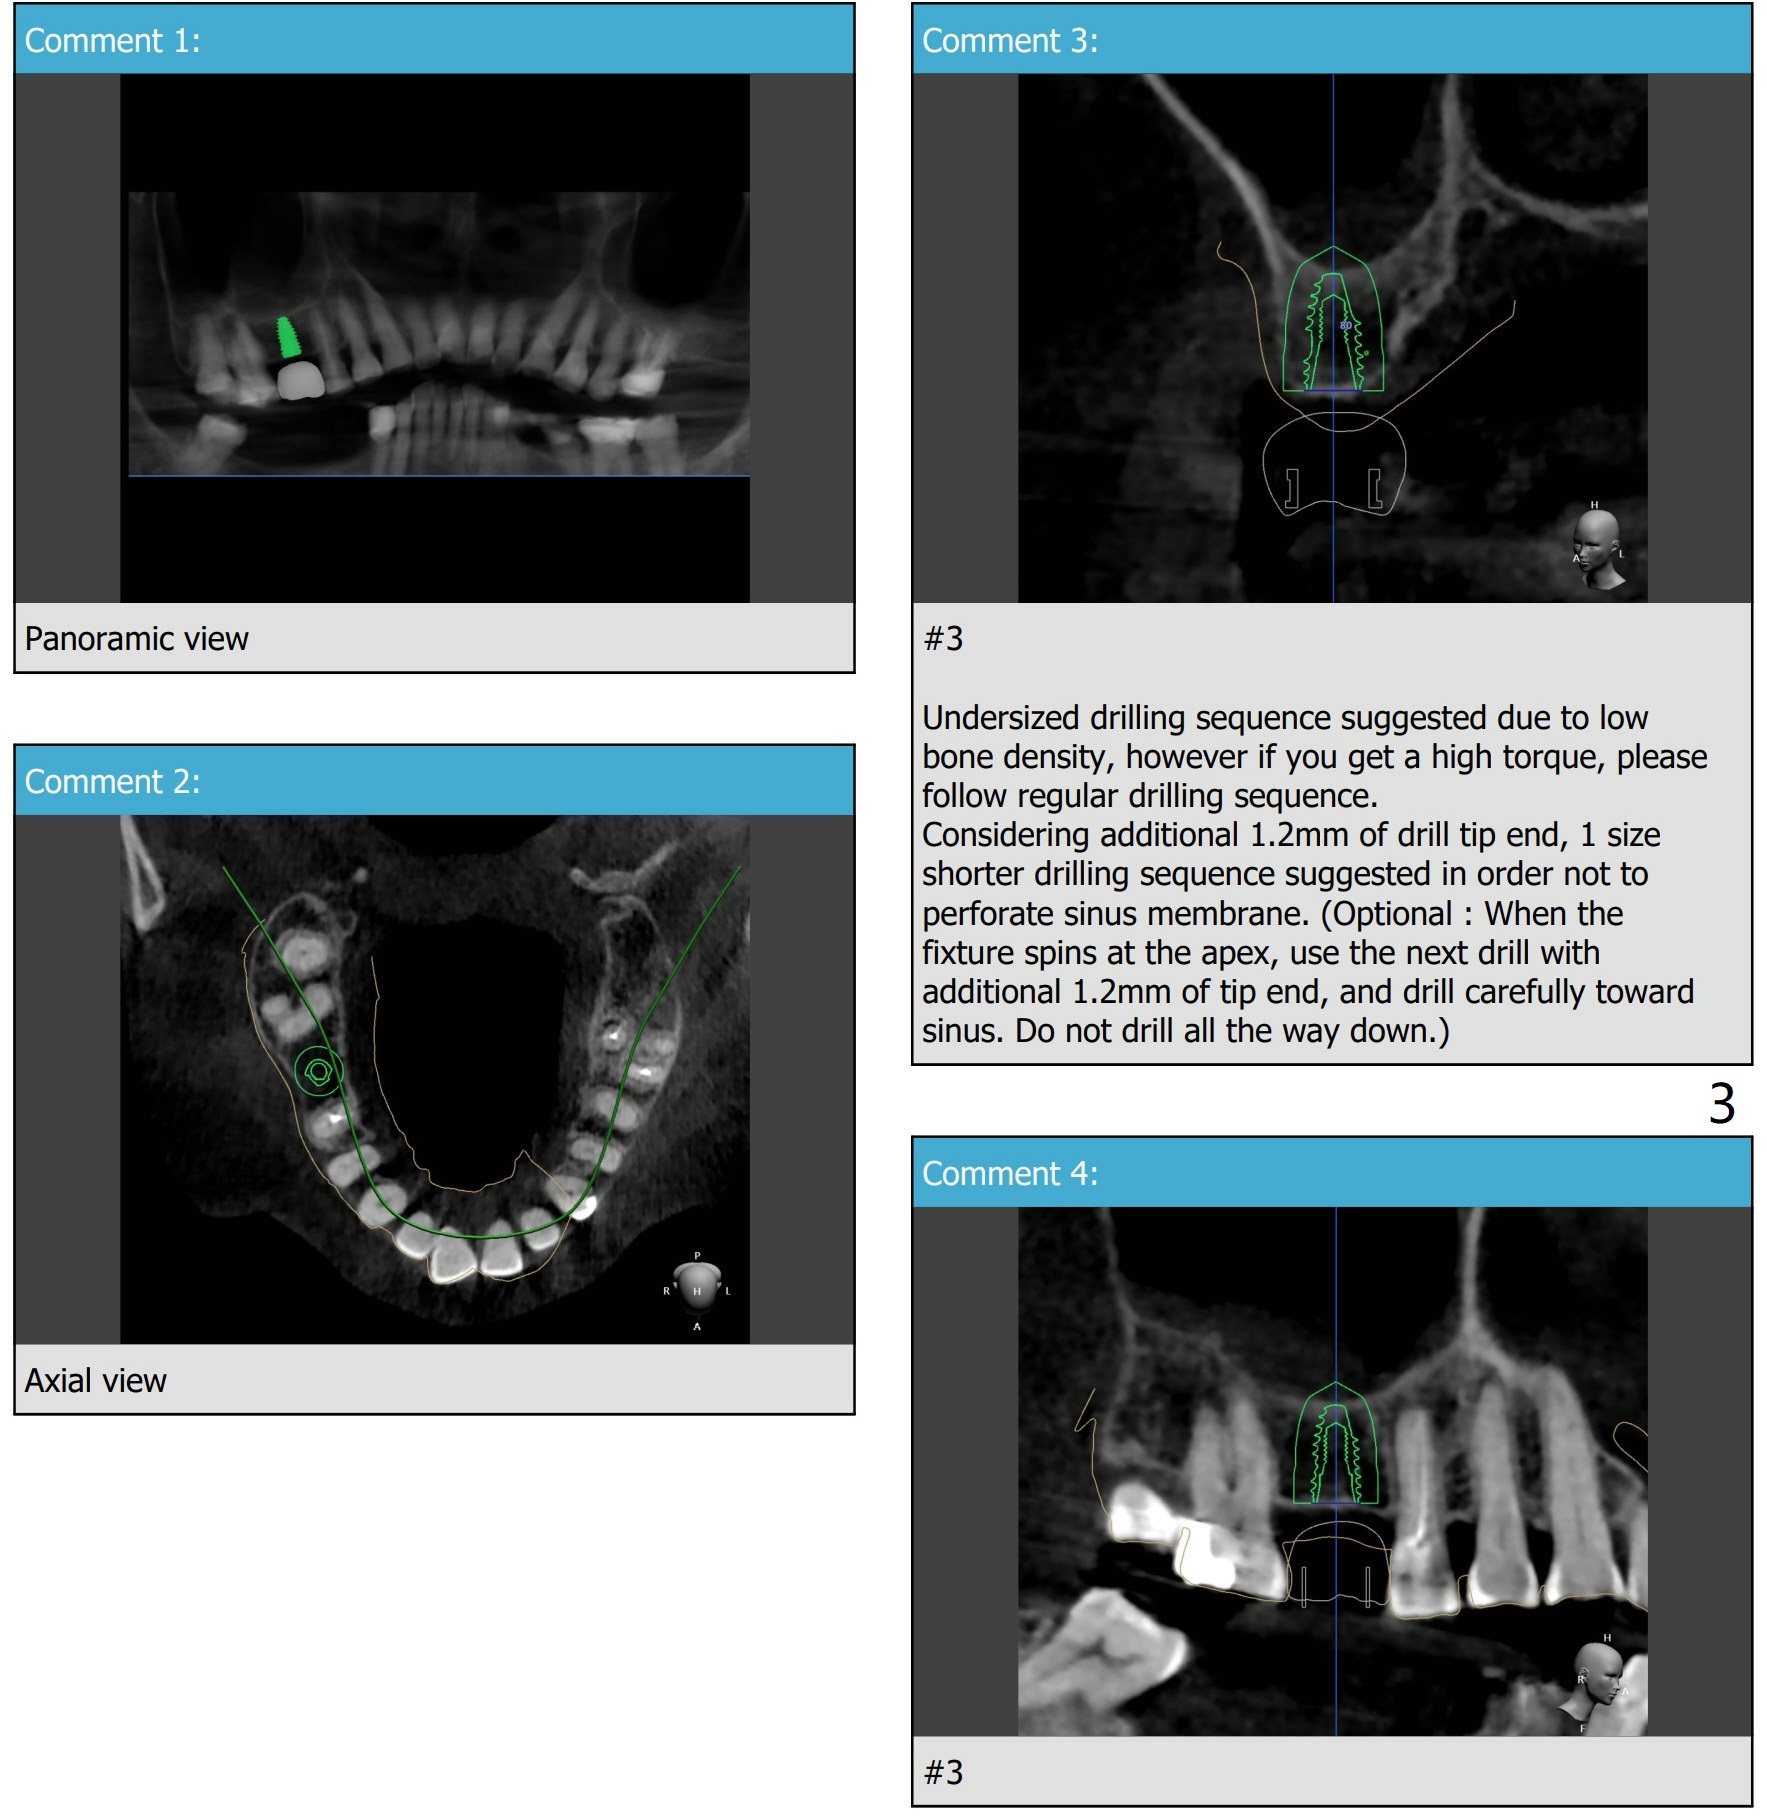

Underdrill for Sinus

A 81-year-old woman

Xin Wei, DDS, PhD, MS 1st edition 06/18/2021, last revision 07/13/2021